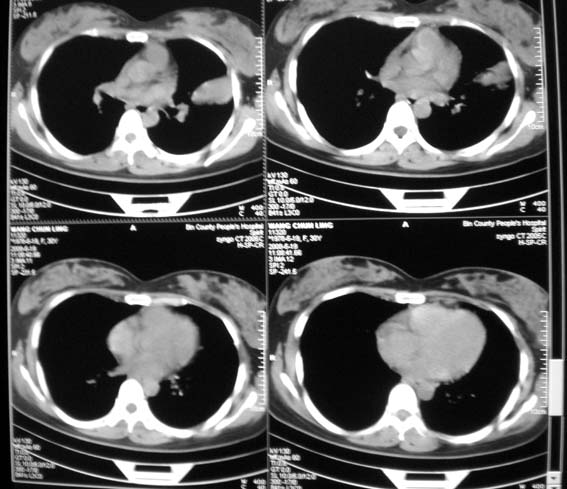

标题: CT13529:肺结核?请会诊!

女,30岁,怀孕后3个月,拍片时肺结核,抗结核治疗4个月复查。

前段支气管通畅,但尖后段支气管闭塞,建议支纤镜除外肺癌,有原片吗,对比一下了。

结核.前段支气管通畅,但尖后段支气管闭塞,建议支纤镜除外肺癌

纵隔淋巴结肿大,见意出外占位

既然抗结核治疗4个月,一定做了结核相关检查,建议与原片比较看治疗效果,也可结合纤支镜取病理检查。